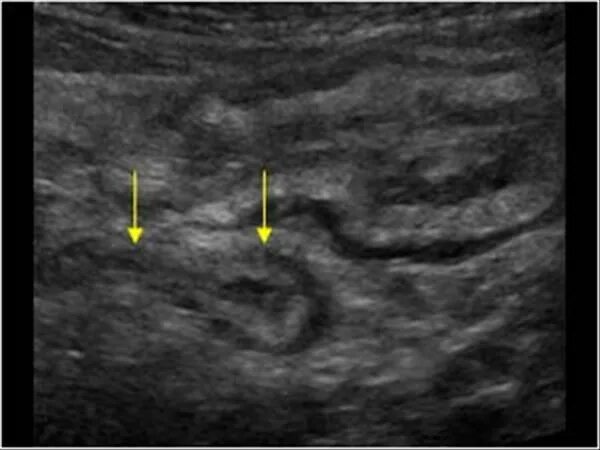

Аппендицит на узи можно ли